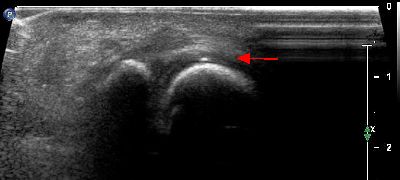

Calcificazione intra articolare (img. 01) Calcificazione intra articolare 01

Calcificazione intra articolare (img. 02) Calcificazione intra articolare 02

Calcificazione intra articolare (img. 03) Calcificazione intra articolare 03